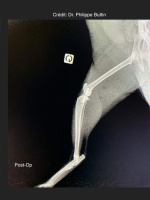

Radiologické snímky